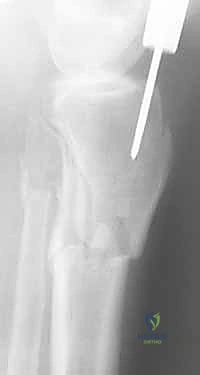

يبدأ التشخيص بالفحص السريري الدقيق لتقييم حالة الجلد، النبض، والأعصاب. يتبع ذلك إجراء الأشعة السينية (X-rays) من زوايا متعددة لتحديد موقع وشكل الكسر بدقة. في حالات الكسور المعقدة أو التي تمتد إلى مفصل الركبة أو الكاحل، يطلب البروفيسور هطيف إجراء أشعة مقطعية (CT Scan) للحصول على صورة ثلاثية الأبعاد تساعد في التخطيط الجراحي الدقيق.

باستخدام جهاز الأشعة السينية المتحرك داخل غرفة العمليات (C-arm Fluoroscopy)، يتم سحب الساق وإعادتها لوضعها التشريحي الصحيح (Reduction) دون فتح منطقة الكسر.